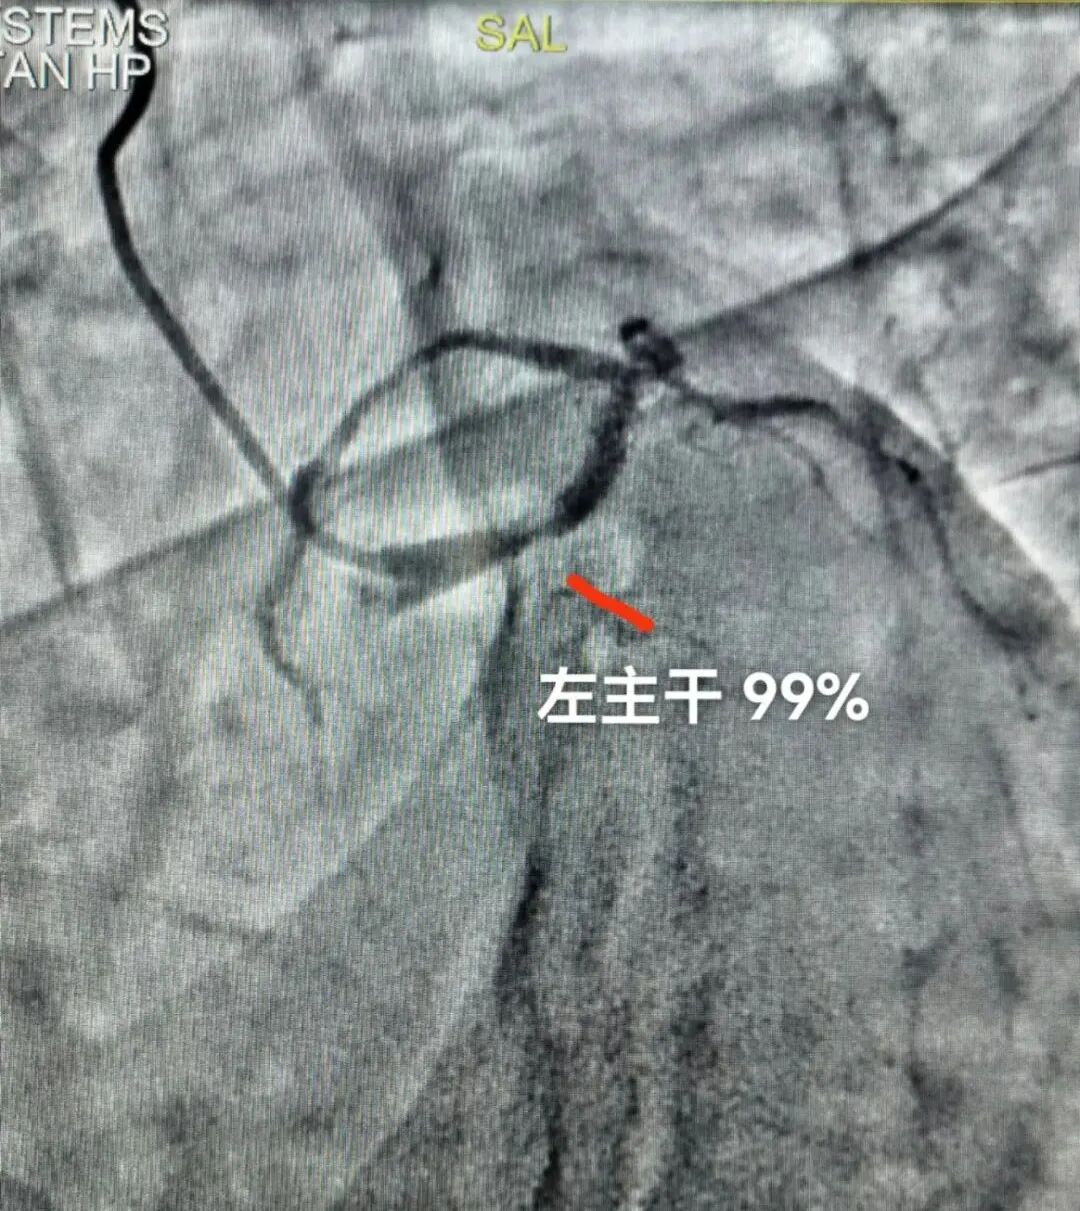

自积水潭医院新龙泽院区急诊开业后,急诊-心内科急性心肌梗死绿色通道顺利启动,成功抢救多名危重急性心肌梗死患者。 47岁的何先生于年前因突发心前区疼痛,由120送入我院急诊,然而刚送至医院即发生心脏骤停,呼吸及意识丧失,经心脏按压,气管插管等恢复心跳,心电图显示非常弥漫的ST段压低,提示心肌缺血范围非常广泛。患者经抢救后,于三天后成功脱离呼吸机并转至新龙泽院区CCU。 然而在准备进行介入手术的过程中,由于重症左心衰出现呼吸极度困难,再次进行气管插管,呼吸机辅助呼吸。超声心动显示患者的射血分数仅为38%,并伴有二尖瓣的重度反流。虽然二次抢救将何先生从死亡线上拉了回来,但心电图及相关检查都提示患者冠状动脉病变严重,而且合并严重左心功能不全及肺部感染。此时手术风险非常大,团队经过紧密磋商,决定继续稳定病情,选择合适时机进行介入治疗。 很快在团队的精心治疗下,何先生脱离呼吸机,病情也进一步稳定,顺利进行了冠脉造影。 然而冠脉造影提示他的生命之树从根部即左主干就狭窄99%,也就是说患者只靠着一个生命线活着,如果手术有任何闪失,病人在当时就会出现循环崩溃。经与患者家属协商,医务部主任助理汪蓓紧急调动全院资源,在麻醉科及ICU王郝副主任的支持下,心内科刘巍主任携介入团队于ECMO辅助下,成功开通LM99%狭窄,植入一枚支架,手术进行顺利,病人症状明显改善,仅仅3天后就好转出院。 术前 术后 1月9日午夜 11:30 ,120 送一名持续胸痛的老年女性到新龙泽院区急诊。病人来医院前,心内科主任刘巍就于第一时间得知,经远程心电图诊断考虑急性心肌梗死。刘巍主任迅速调动值班三线赵颖主治医师,绿色通道值班人员韩昊副主任医师和陈游洲主治医师以及介入导管室护理人员及技师,与急诊科当班人员配合,快速开通绿色通道,紧急将患者送入导管室进行冠脉造影及介入治疗。 患者的冠脉造影显示三支病变,此次的罪犯血管为前降支,狭窄95%并且伴有血栓及严重钙化。心内科介入团队克服了重重困难,成功为患者开通前降支并植入支架,患者症状立刻缓解,送至CCU进一步诊治。 术前 术后 急性心肌梗死是所有冠心病最严重的表现,临床症状为持续不缓解的剧烈胸痛,可能伴有恶心呕吐,腹痛,牙痛,甚至晕厥及猝死,因此在第一时间开通血管刻不容缓。我院在回龙观院区及新龙泽院区均配备有完善的急性心梗绿色通道,团队技术成熟,每年完成心脏介入治疗手术近1000例,急诊抢救近350例急性心肌梗死患者,已经成为京北地区心血管急症患者生命的坚实保障。 抢救团队与康复患者(一排右三)合影